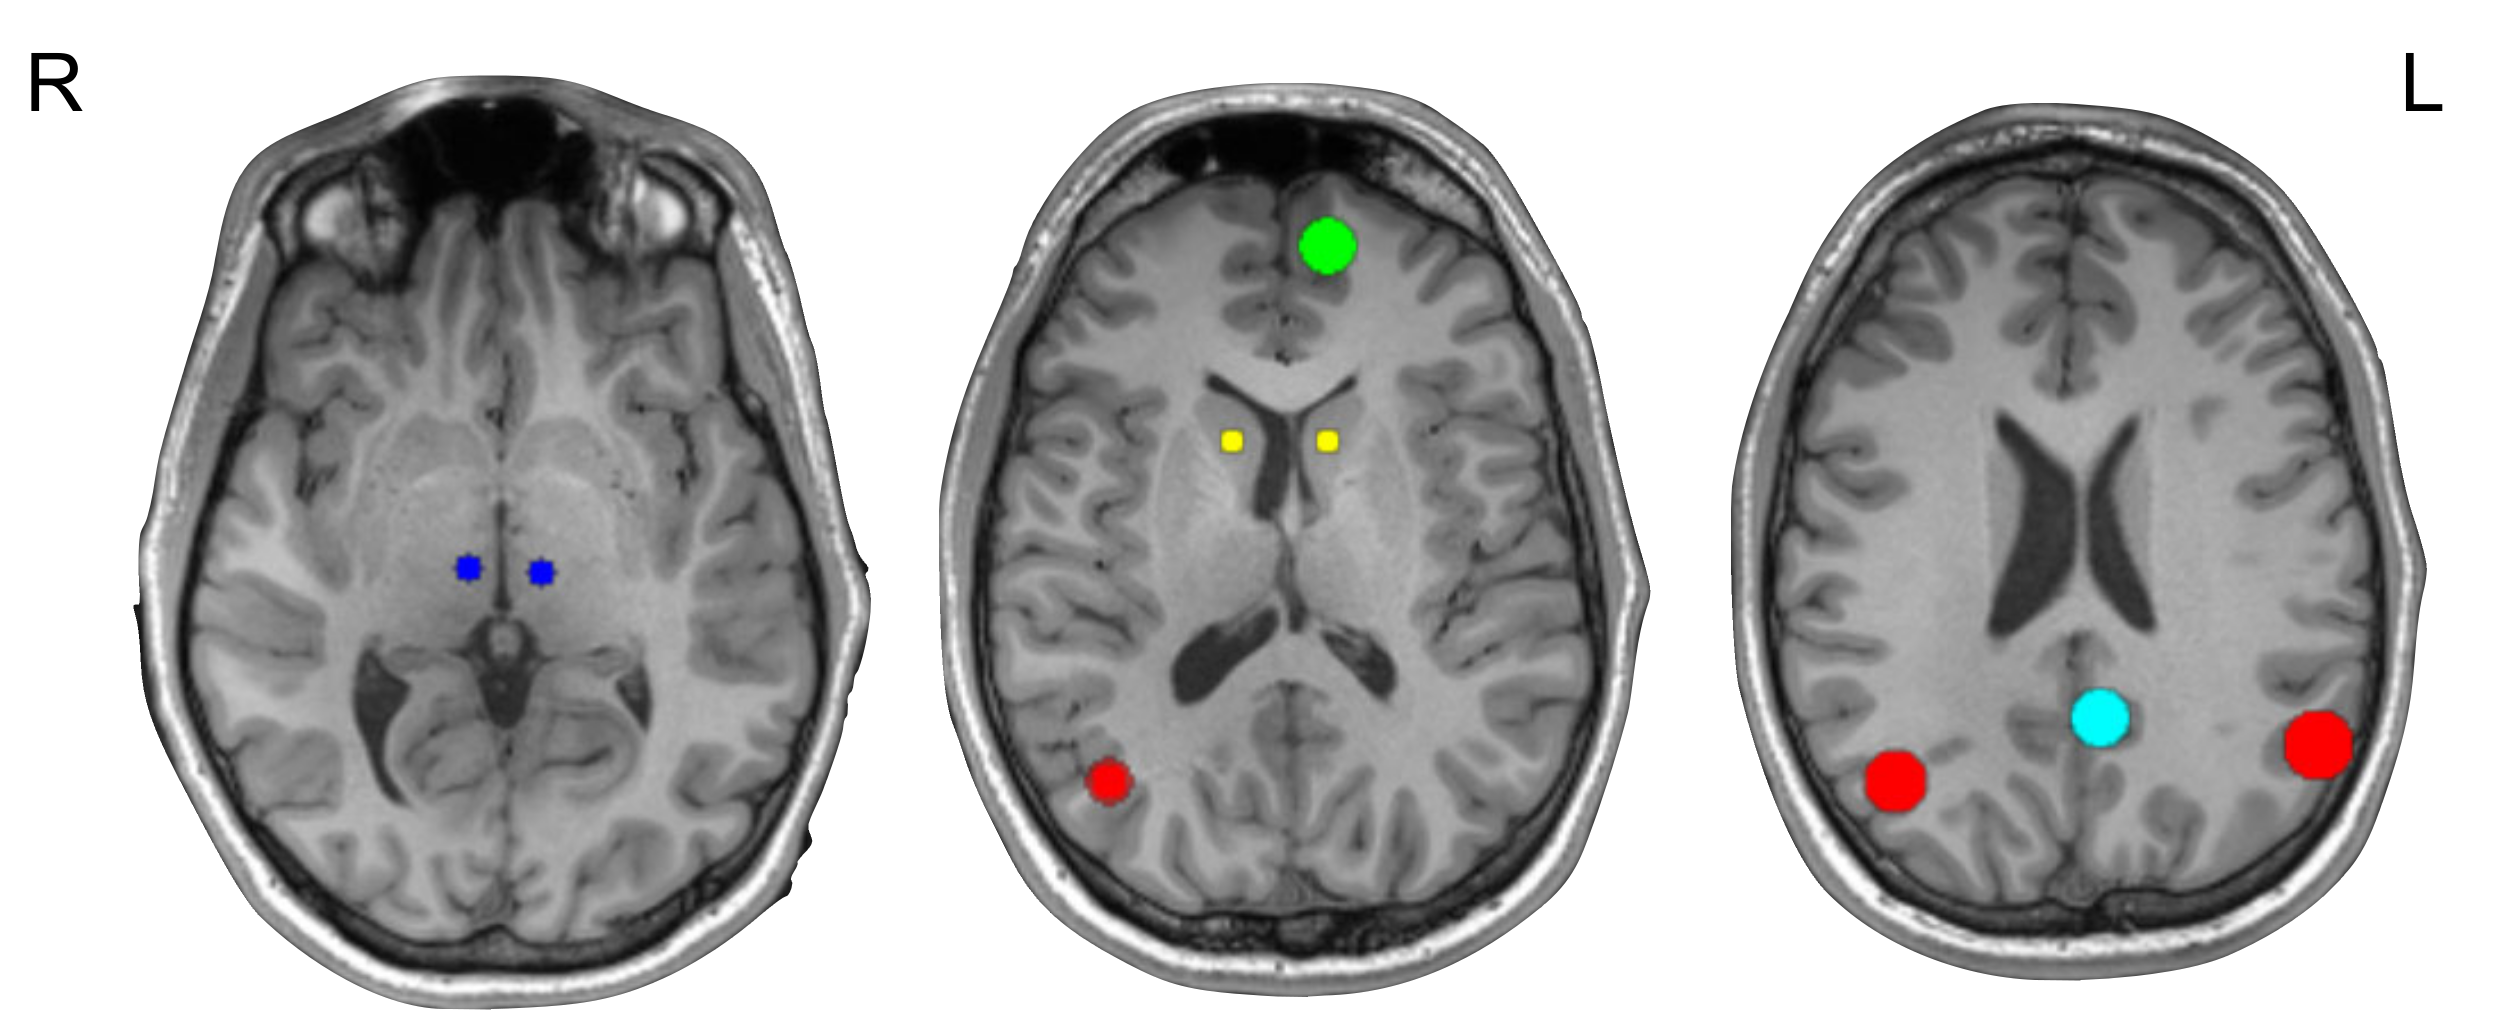

2.4. Selection of ROIs